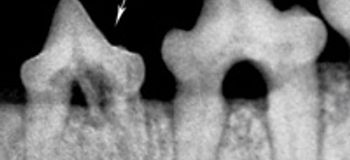

Exam and tooth resorption is only detectable on a radiograph. Tooth resorption when examining a pets mouth is seeing red tissue on the tooth for active. Ad Ensure Your Pet Is Happy And Healthy And Enjoy Savings On Pet Medications.

We still do not know what causes tooth resorption in cats. Topical Therapy for Skin Conditions in. The lesions are small and close to the base of the.